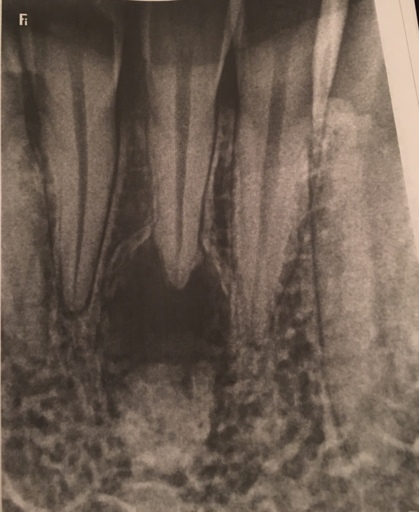

Does it look like I may need braces?

Hi, I have an upcoming orthodontist appointment next month because my mom is worried about my teeth. I’m nervous to know if I’ll need braces or not and I want an idea of what the Ortho would say. What do you think?

You are a great candidate for orthodontic treatment. It appears that your maxillary (upper) teeth are slightly flared, bringing these teeth back into proper alignment will close the space between your maxillary and mandibular front teeth. In the bottom right picture, it is hard to see if your posterior (back) teeth are touching. If they are, then you are considered to have an "open" bite. Your upper front teeth should slightly overlap your lower front teeth allowing you to bite into and tear your foods easily. More than likely, the orthodontist will recommend a full orthodontic treatment case placing you in treatment for 12-18 months, followed by retention.